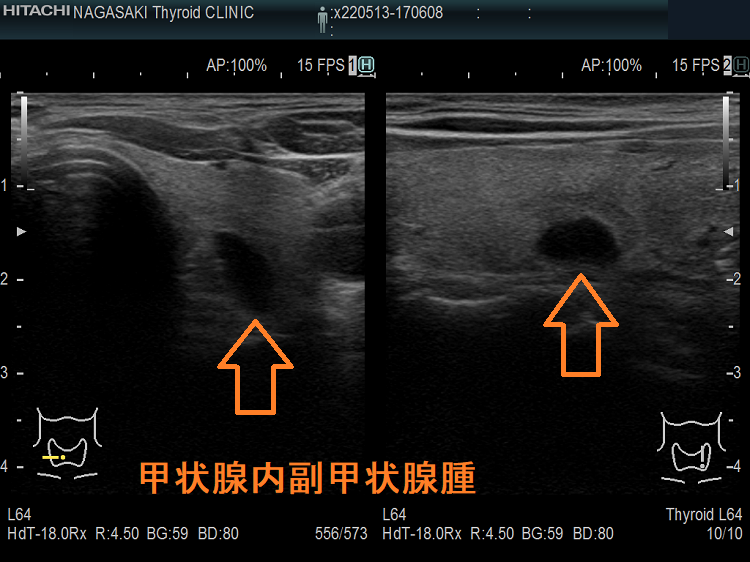

甲状腺内副甲状腺腫は、原発性副甲状腺機能亢進症の1.4 ~ 2.1%を占めます[Surgery. 2009 Dec;146(6):1144-55.]。

甲状腺内副甲状腺腫は、超音波(エコー)検査で甲状腺腫瘍と形態的に鑑別できない場合があります(実際は下の写真のように診断できていますが・・)。特徴的な超音波(エコー)所見は、腹側の高エコーで感度86%、特異度100%です[Surgery. 2012 Dec;152(6):1193-200.]。さらに、99m-Tc MIBIシンチグラフィーで取り込み(集積)があれば甲状腺内副甲状腺腫と診断できます。

99m-Tc MIBIを取り込まない甲状腺内副甲状腺腫もあるため、穿刺細胞診を行い、針先洗浄液でインタクトPTHを測定(FNA-PTH)。甲状腺内副甲状腺腫は、甲状腺が周囲にあるため、針に沿った副甲状腺細胞のばらまき(播種)・出血の危険が少なくなります。

腺腫様甲状腺腫に合併する甲状腺内副甲状腺腫

腺腫様甲状腺腫に合併する甲状腺内副甲状腺腫は、腺腫様結節と鑑別が難しいだけでなく、多腺性(5-6腺)のケースがあります。